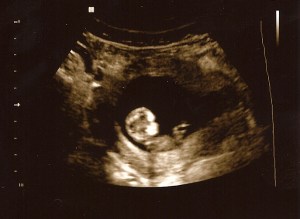

As of tomorrow, I will be 11 weeks along. Its hard to believe that six weeks have already gone by since we learned of this new “occupant”. My, how time does fly! We had another OB appointment today. Everything had gone smoothly until our doctor tried to audibly find the heartbeat. After trying for a little while, we went next door for an ultrasound…just to make sure nothing was wrong.

No wonder she couldn’t find the beat at first – our little one was bouncing all over the place! As soon as she put the machine on, Baby Leino’s image popped onto the screen, bouncing & waving as though it had not a care in the world. Seeing the life in our child, now looking more like a baby rather than a peanut, hit me in a way I did not expect as it all became much more real to me. At one point, it looked as though it could be smiling!

Since this pregnancy is considered high risk (because of our history with Isaac), there will be some testing & detailed ultrasounds in the weeks to come. A perk of being high risk – you get to see your growing child so much more! This child is already a blessing. We are praying for continued growth, health, & protection as he/she matures each day. At least we know this: our little one is full of energy!